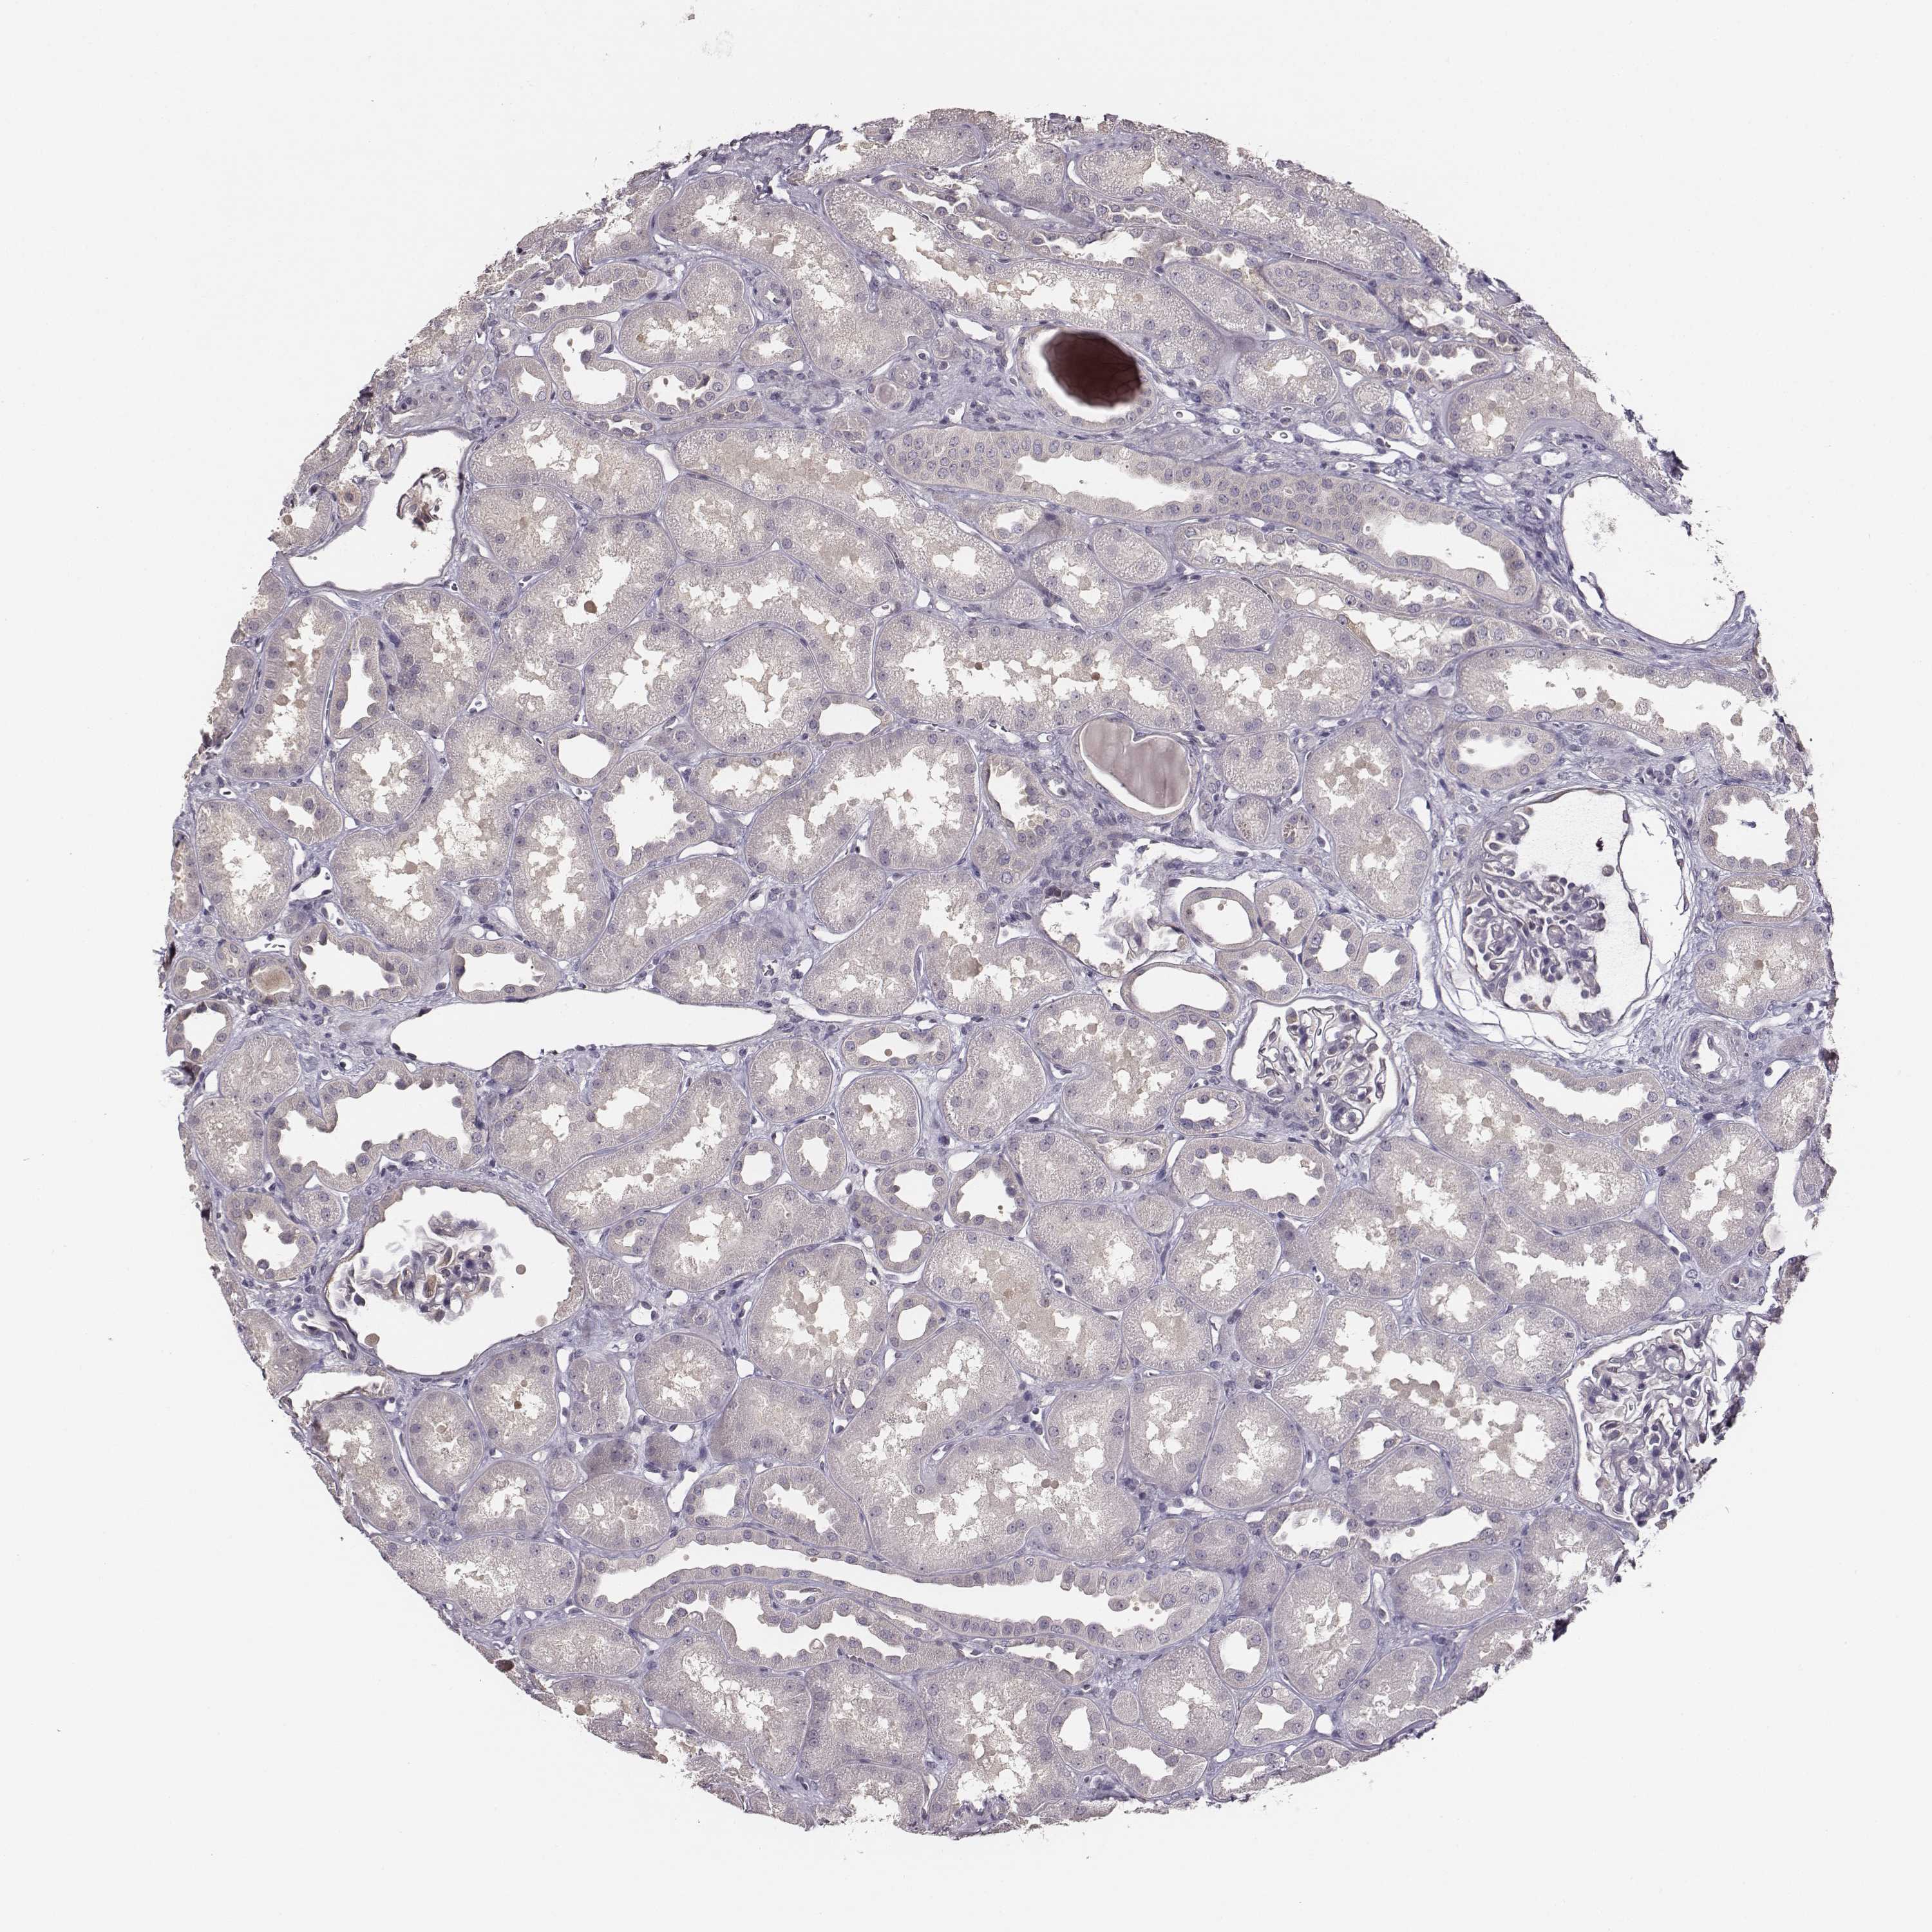

KAAG1